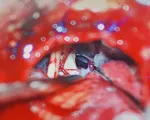

VTV.vn - Theo hãng tin Sky News, hơn 500 chiếc răng đã được loại bỏ khỏi miệng một cậu bé 7 tuổi ở Ấn Độ sau một cuộc phẫu thuật kéo dài 5 tiếng đồng hồ.

Khi cấu trúc trên được loại bỏ, các bác sỹ đã mở chúng ra và tìm thấy 526 chiếc răng đủ kích cỡ ở bên trong. Các bác sỹ chưa xác định rõ nguyên nhân của trường hợp này, nhưng có thể là do di truyền.